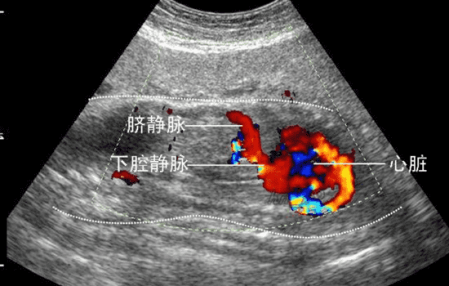

二维彩超能够观测到器官内部血液流动情况,彩超能够直观成像,显示更清晰,结果也更快速,在孕妇b超**中有着非常大的作用。孕妇做**是时候采用彩**超**,可发现异常血流,为诊断胎儿先天性心脏缺陷提供了诊断依据。

其实可以把普通b超和彩超归为一个范畴:普通b超就像黑白照片,彩**超就是在b超的功能上多了一个彩色多普勒功能(CDFI),可以在黑白图像上看到彩色的血管,当彩色多普勒功关闭的情况下,它依然是黑白b超超声。